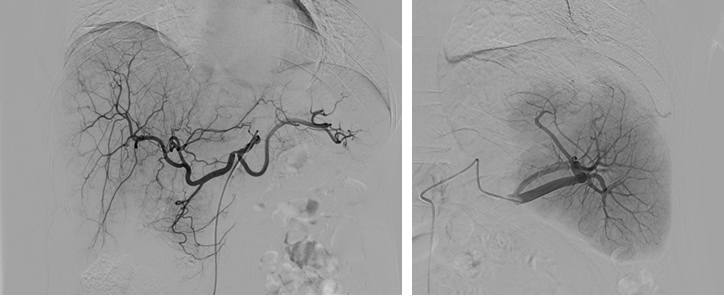

肿瘤介入,纤毫毕现

“零噪声”DSA“让肿瘤供血血管无所遁形”

在肿瘤介入手术中,“零噪声”DSA凭借比传统设备成像清晰度提升4.2倍与智能血管增强技术,显著提升了对肝癌肿瘤微小供血动脉(直径<0.3mm)的识别能力,为精准栓塞提供革命性支持。